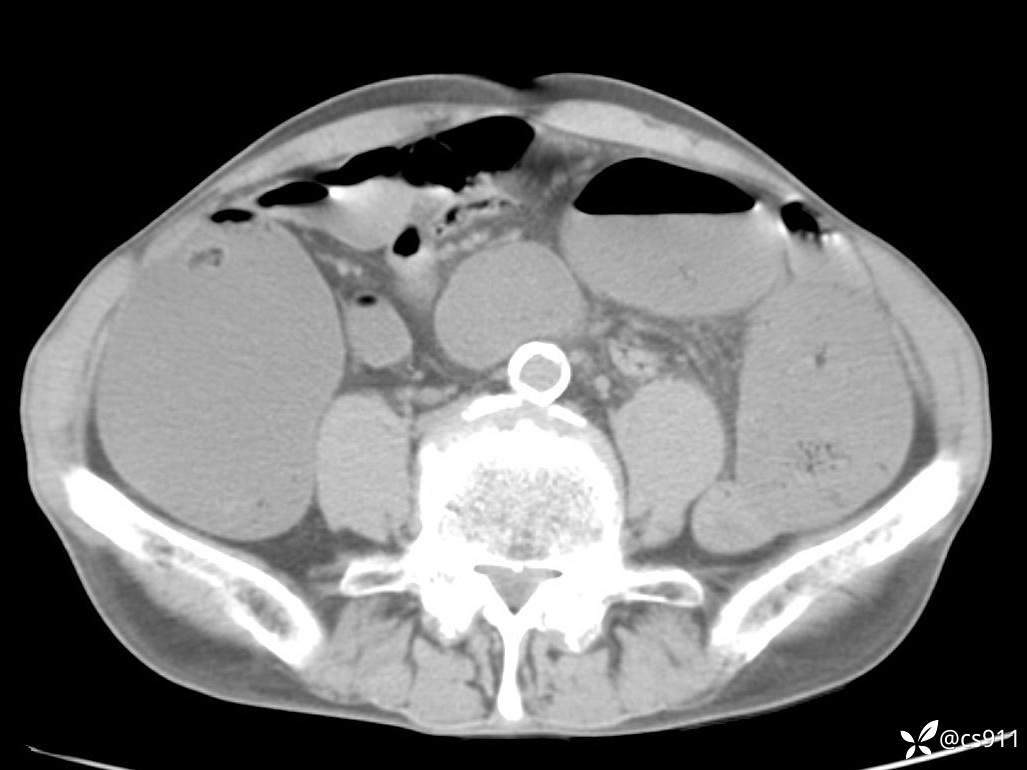

急腹症之急诊CT,原因?答案公布

男,77岁,腹痛、腹胀伴恶心呕吐1天。呕吐胃内容物,非喷射性呕吐,有咖啡色样胃内容物,诉有胃穿孔病史。查体:全腹平,下腹部压痛,全腹无反跳痛,叩诊呈浊音,移动性浊音阴性,肠鸣音减弱,1-2次/分。肛检:直肠未扪及明显肿物,可触及大量粪块。

T 36.6℃ P 80次/分 R 26次/分 BP 100/60mmHg

白细胞(WBC) H 14.55 10e9/L 4-10

中性粒细胞百分率(NEUT%) H 85.7 % 40-75

血淀粉酶(AMY) HH 1859 U/L 35-135

癌胚抗原(CEA) H 27.44 ng/ml 0-5

呕吐物 潜血试验 * 阳性 阴性

患者轮椅入室检查神志清楚, 能配合摆位和呼吸